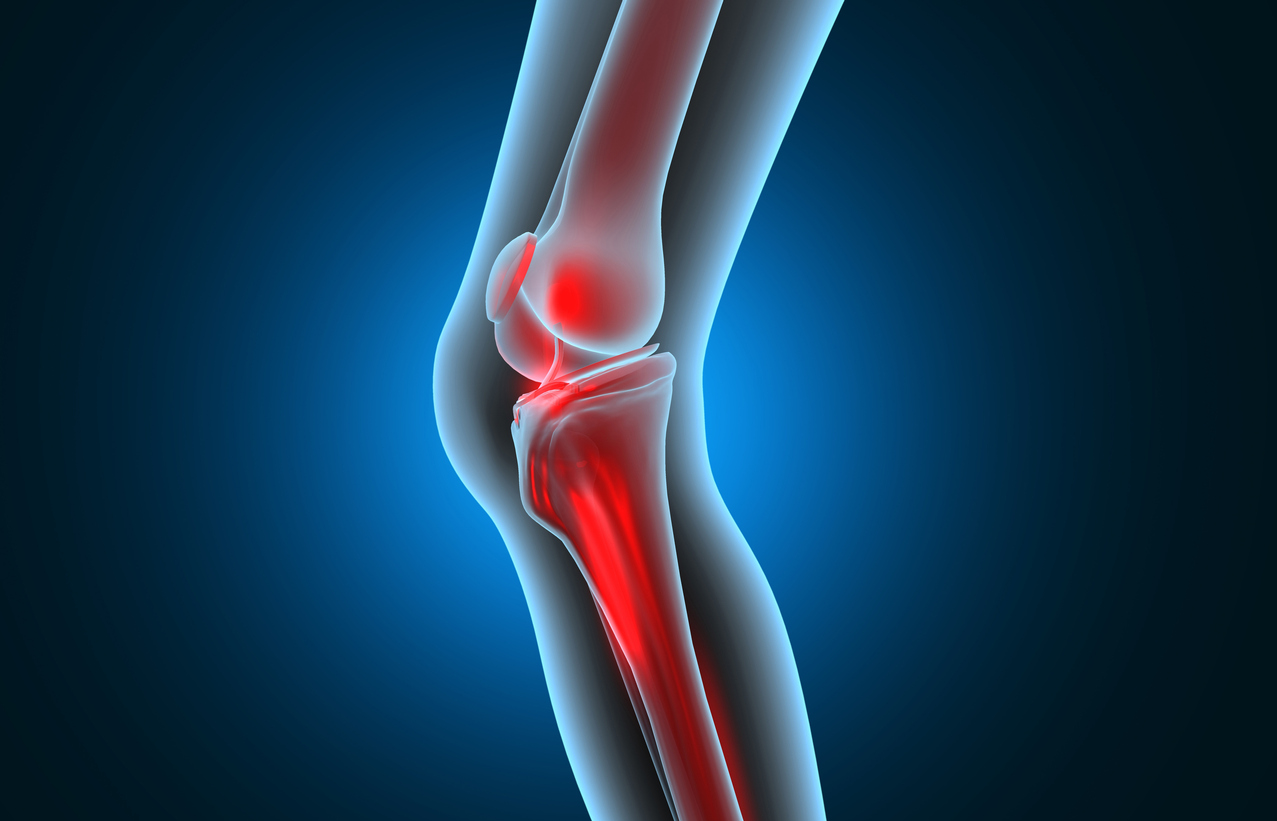

Cortisone Shots vs. Knee Surgery: Exploring Treatment Options

Dealing with Knee Pain Knee pain can be debilitating and significantly impact one’s quality of life. When faced with knee pain, individuals …

Treating an Old Knee Injury

An old knee injury can be a chronic and painful condition that can significantly affect your daily life. It is crucial to …